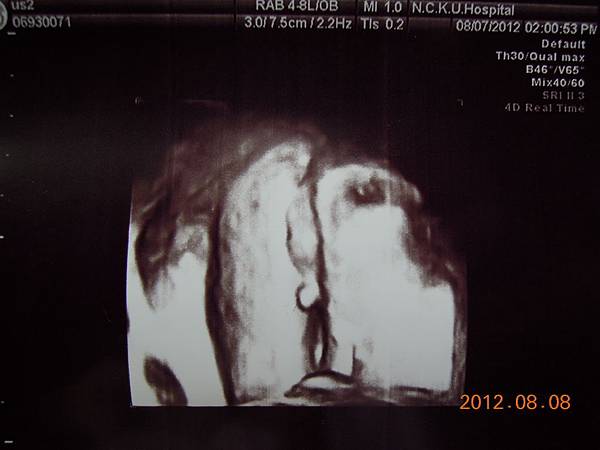

這個好像是逼逼的臉吧~~

這張可以看到他的厚嘴巴~~我回來拿給Horry看,說他跟你的嘴巴一樣ㄟ~~他聽了一直笑~~~